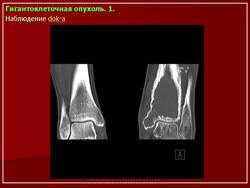

Остеобластокластома (ячеистая форма) дистального эпиметафиза лучевой кости

а — прямая проекция;

б — боковая проекция.

Дистальный конец лучевой кости умеренно «вздут», преимущественно в ладонно-локтевую сторону. Корковый слой кости на этом уровне значительно истончен, но всюду сохранен; контуры его крупноволнистые. Структура «вздутого» участка имеет крупноячеистый рисунок. Дифференциальная диагностика остеобластокластомы с костной кистой трудна и базируется в основном на клинических данных. Для кисты характерно более спокойное, безболезненное течение. Решающее значение имеет костная пункция.